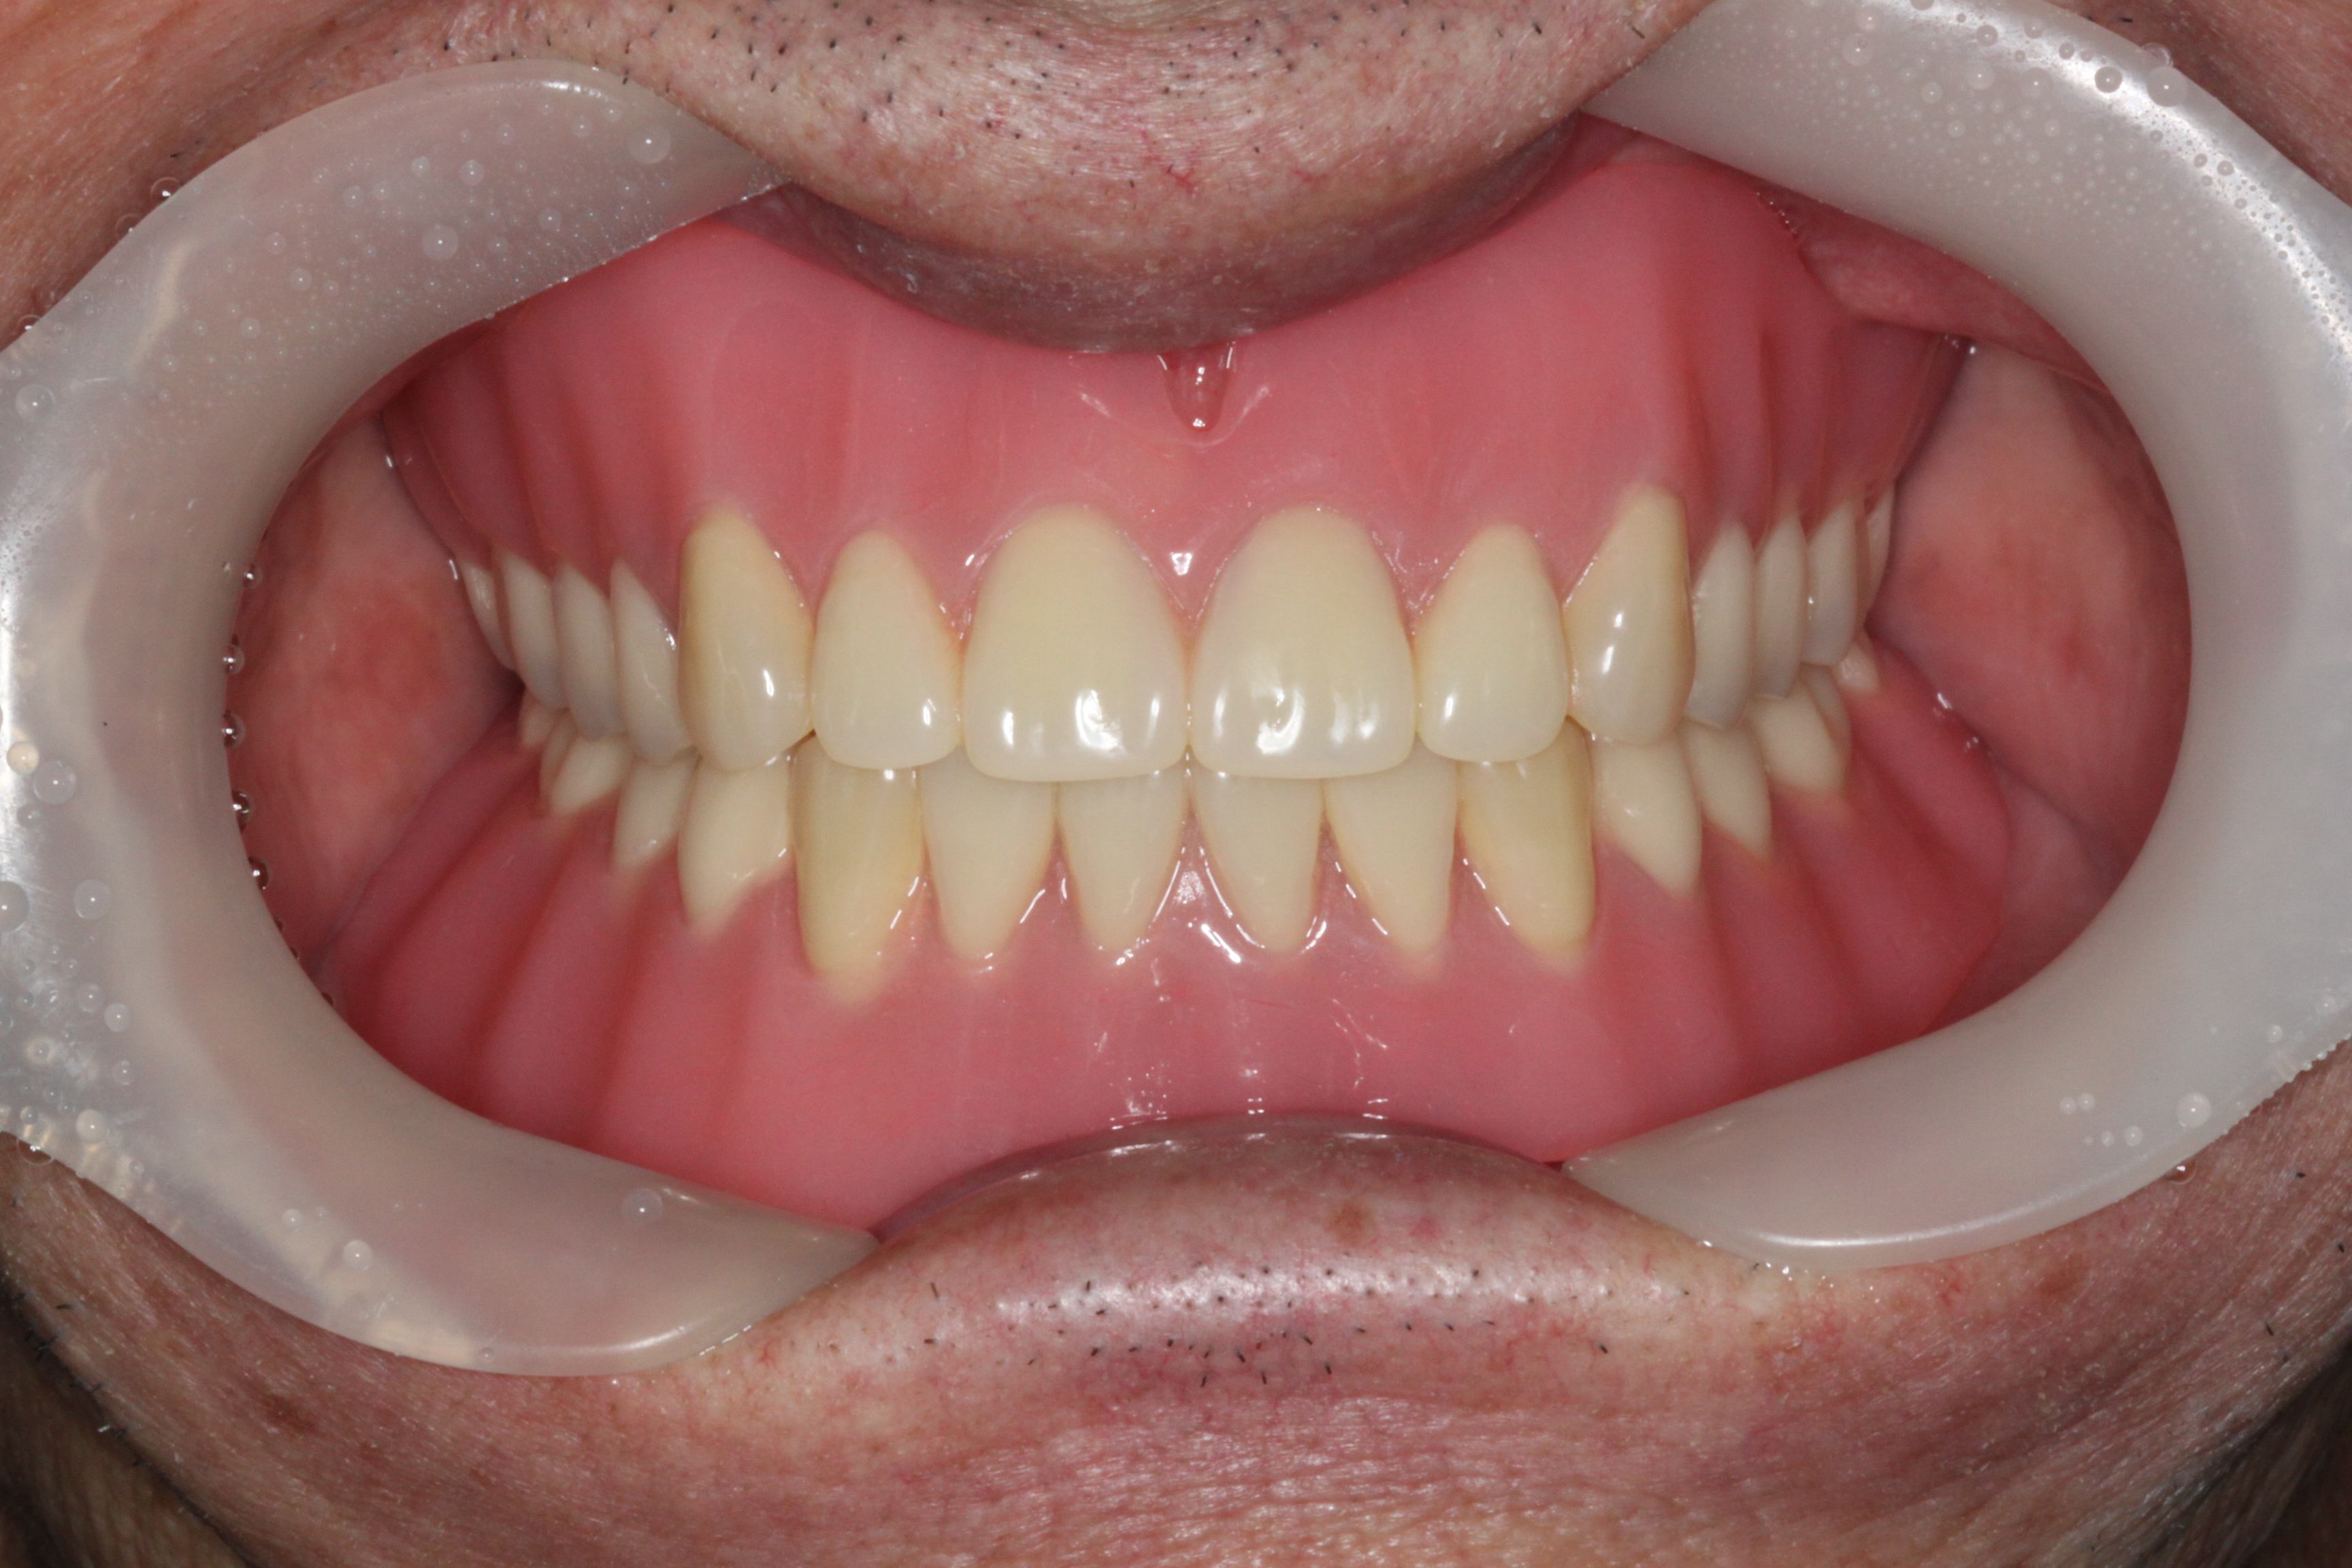

BEFOREAFTERBEFOREAFTER(식립)AFTER(착용)

임플란트 틀니